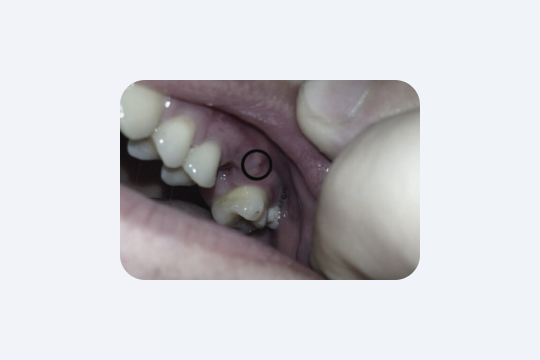

Отже, ви тільки що вийшли з катедри стоматолога. В роті трохи нудне відчуття, отже, варто бути обережним. Яка їжа підходить одразу після видалення зуба? Взагалі краще забути про їжу на декілька годин. Чому? Ну, є декілька причин.

- Згусток крові: Він дуже делікатний у перші години. Їжа може його зруйнувати.